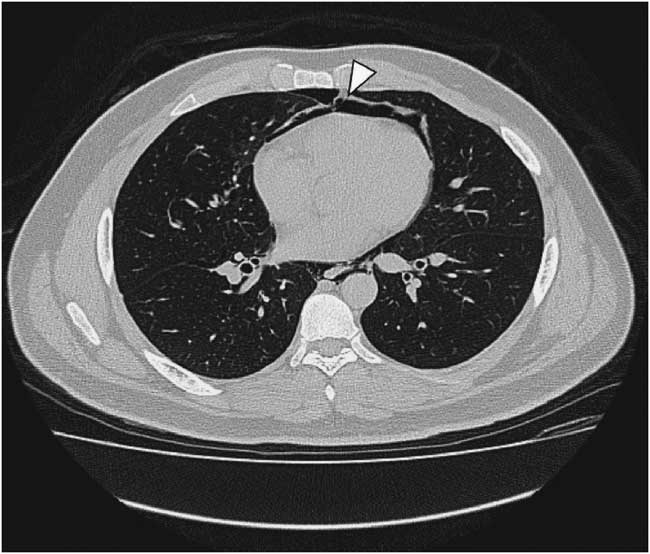

A 22-year-old male presented to the emergency department due to progressive odynophagia and dysphagia. He underwent a left third mandibular molar extraction at the dental clinic a week prior. At the emergency department, vital signs were normal except tachycardia (114/min) and tachypnea (22/min). A physical examination revealed bilateral neck tenderness with crepitus on palpation, no stridor or acute airway compromise signs. Laboratory data showed leukocytosis (white blood cell count, 19000/cumm; segmented, 91%) and elevated C-reactive protein (1.07 mg/dL). Radiographs showed the presence of prevertebral emphysema on the C-spine lateral view (Figure 1) and subcutaneous emphysema with pneumomediastinum on the chest posteroanterior view (Figure 2). A non-contrast computed tomography (CT) scan confirmed the radiographic findings; additionally, there was gas collection over the pericarotid, pericardial (Figure 3) and extradural spaces (Figure 4). Because there was no CT evidence of infectious signs and clinical features were stable, conservative treatment with intravenous amoxicillin/clavulanic acid was given for a week. Clinical symptoms improved, and a follow-up CT showed no residual gas.

Figure 3 Non-contrast chest computed tomography shows pneumopericardium (arrowhead).

Although subcutaneous emphysema is a rare complication following dental procedures, with mostly benign and self-limiting sequelae, it may progress to fatal consequences such as cardiac tamponade, air embolism, pneumothorax, and mediastinitis.Reference Goodnight, Sercarz and Wang 1 There have been reports correlating subcutaneous emphysema and dental treatments with the use of air turbine hand-pieces and air syringes.Reference McKenzie and Rosenberg 2 , Reference Arai, Aoki and Yamazaki 3 CT is useful to detect the precise extension of gas dissection, such as pneumomediastinum, pneumopericardium, and pneumorrhachis, in this case.Reference Ehmann, Paziana and Stolbach 4 Most importantly, CT can evaluate the complications of extensive emphysema or infectious process. In addition, it can guide clinical treatment decisions like the need for urgent tracheostomy or fasciotomy.